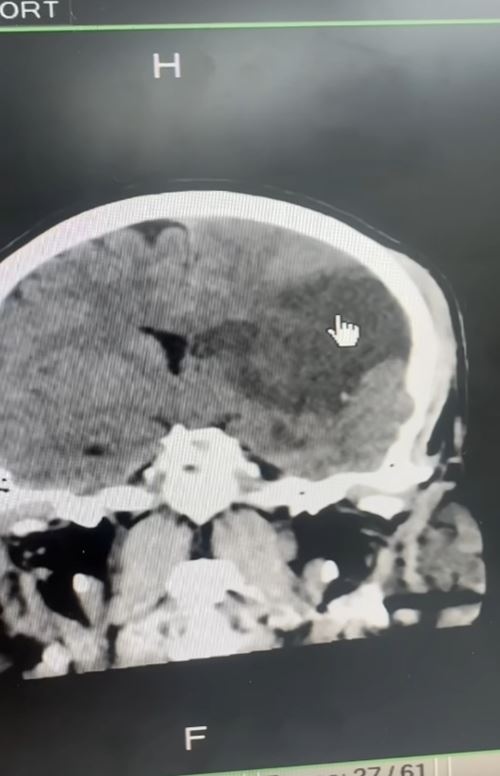

หมอสแกนสมอง พบเนื้อสมองบางส่วนตาย ตรงสีดำในภาพ CT แสดงว่าเกิน 8 ชั่วโมง ปกติคนเรามีเส้นเลือดไปเลี้ยงสมอง 4 เส้น คือ หน้าขวา หน้าซ้าย หลังขวา และหลังซ้าย แต่คนไข้รายนี้เส้นเลือดหายไปเหลือ 3 เส้น เกิดจากเส้นเลือดที่คอปริแตก ลิ่มเลือดไปอุดตันเส้นเลือดตัวเอง เนื่องจากคนไข้เส้นเลือดสมองตันในเวลากลางคืน เลยเวลาที่จะทำอะไรได้ จึงต้องผ่าตัดเปิดกะโหลกเพื่อลดแรงดันในสมอง